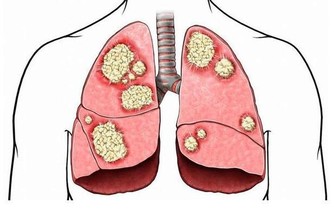

邱大姐,今年64歲。半年前,她出現頭暈、乏力,到醫院檢查,有嚴重的貧血。前段時間病情加重,又到省立醫院就診,發現白細胞、血小板均有減少,進一步檢查確診為「骨髓增生異常綜合症」。

這個病名很專業,可能很多非血液科的醫生都沒聽到過。說直白點,就是患者的造血幹細胞惡性克隆,導致無效造血。白血病,我們通常稱之為血癌,骨髓增生異常綜合征其實也是一種血液腫瘤。這種病預後很差,有30%左右的患者會發展為白血病。

研究認為,苯是染髮劑中最基本的化學物質,對造血系統具有強烈毒性。染髮劑使用一個階段后,苯會沿頭髮浸入頭皮毛細血管,破壞造血系統,引起頭暈、乏力、皮下、內臟和腦出血,更加嚴重的是誘發癌症。近年來,醫學界常使用「染髮白血病」這個名詞,表明了染髮與白血病的關係。